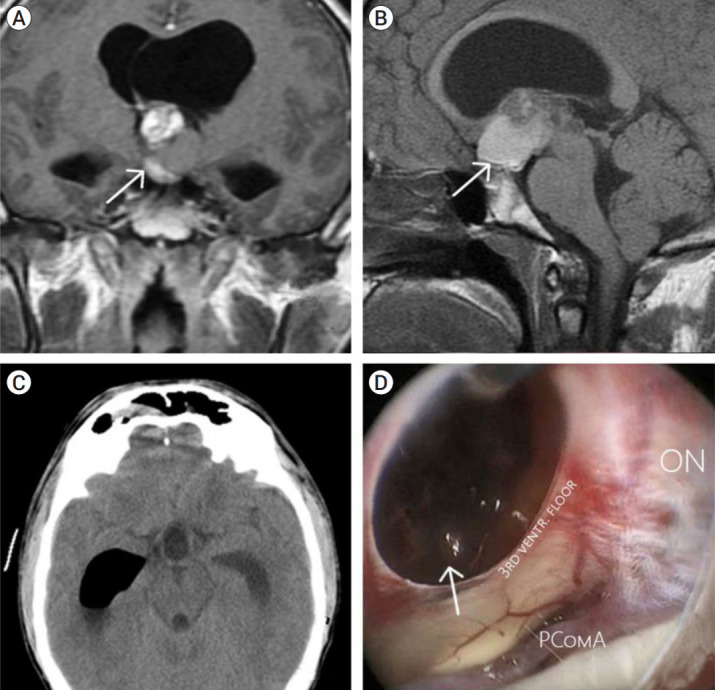

Objective: Optochiasmatic cavernoma is an extremely rare cerebral lesion. They account for approximately 1% of all cavernomas of the central nervous system. Reports on this pathology are limited. Abrupt visual deterioration is a common symptom of the disease. Treatment strategy and visual outcomes after different treatment approaches remain a subject for discussion.

Methods: Patients operated in a period 2005-2021 were analyzed in this study. All patients preoperatively underwent computed tomography (CT) scan, CT-angiography, and magnetic resonance imaging (MRI). Visual function of the patients was assessed pre-op, post-op and at the follow-up. Duration of visual dysfunction was noted as well. Surgical details were also extracted from medical notes. All patients were followed up, and control MRI was performed one month after operation. We assessed surgical series of optochiasmatic cavernomas published for last 10 years. Further comparative analysis with our data was performed.

Results: Five patients were included into this study. There were four men and one woman. Mean age comprised 33.8 years (range 20-48 years). Most patients were admitted to our hospital due to visual disturbances (80%). Visual function improved in four patients. Visual function was unchanged in one patient, lacking visual disturbancies pre-op. Complication developed in one patient.

Conclusions: Optochiasmatic cavernomas are encountered extremely rare. Despite the use of contemporary diagnostic options, differential diagnosis remains challenging. Full diagnostic work-up is mandatory. After the diagnosis is made, surgical treatment should be considered first. Total microsurgical or endoscopic transsphenoidal removal of the optochiasmatic cavernoma is a relatively safe and effective treatment method facilitating improvement of visual function.